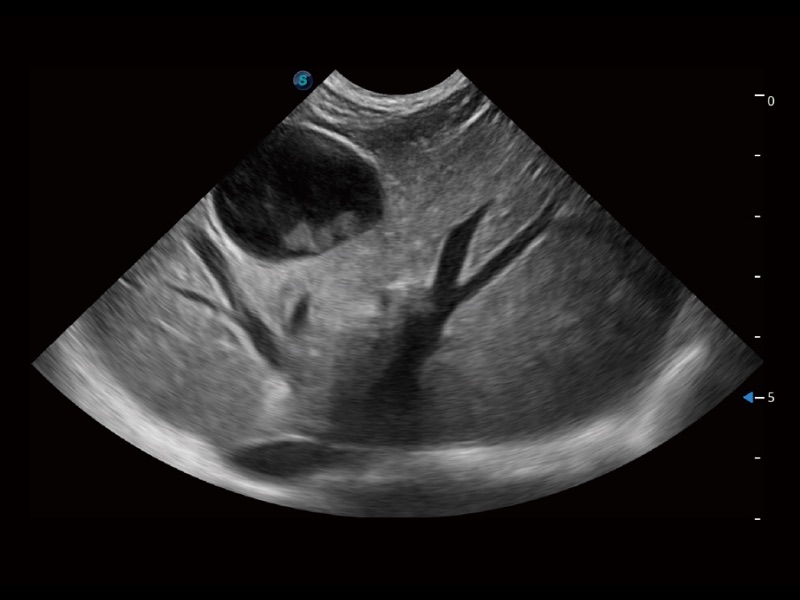

ProPet 70 进一步提升了微米成像算法,更加注重对基础原始图像的还原和保留,在有效减少斑点噪声、增强组织边界显示的同时,避免过度优化丟失真实的解剖信息。

为精细结构及组织边缘提供高清晰度的图像和更大的成像视野。帮助减轻医生的用眼疲劳,快速精准获得测量的数据。